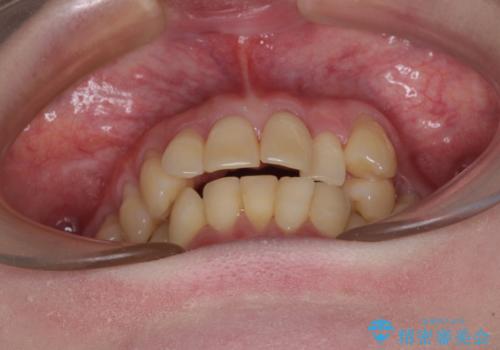

- 八重歯と正中のズレを気にして来院された患者様です。

上顎左側が八重歯になっており、上顎正中が左側にずれていました。

上顎左側の第一小臼歯を抜歯し、補助装置を用いて正中位置を改善しながら八重歯を解消していくこととしました。

下顎前歯が1本欠損していたため、上下正中の位置が合わせるという目標はなく、鼻筋に上顎正中を合わせていくように移動を行いました。